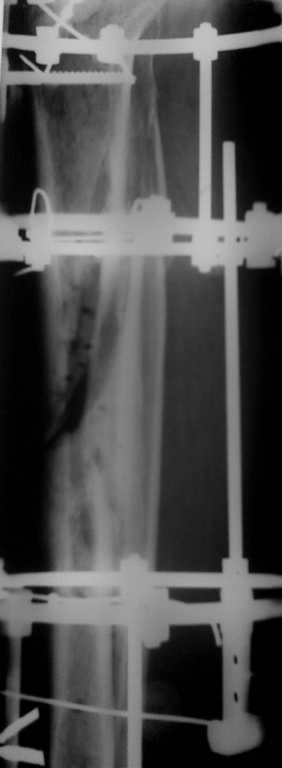

Больному 45 лет. Кость открытая ухе почти год. Повязки с серебросодержащими мазями, Пантенол, получал препараты кальция- простые и Миакальцик. Ситуация такая что один доктор хочет оперировать: иссечения участка кости с остеотомией малоберцевой с компрессией в аппарате. Но ведь есть дефект? Кость и так непокрыта надкостницей, поэтому и нет сращения. Остемиелита так нет. Я предлагаю пластику местными тканями , приживления ран и снятия аппарата. Что посоветуйте? С уважением!

Р> Больному 45 лет. Кость открытая ухе почти год.

Р> Но ведь есть дефект? Кость и так непокрыта

Р> надкостницей, поэтому и нет сращения. Остемиелита нет!

Есть обнаженная кость. Она некротизирована. И нестерильна. А проявлений остеомиелита нет потому, что все открыто. Если дефект мягких тканей закрыть "как есть", то инфекция не заставит себя ждать.

Аппарат действительно можно снять уже, какие-то спайки есть. Но пластика местными тканями здесь - плохая идея. Нужно планировать 1)хорошую некрэктомию с резекцией кости. Возможно, удастся даже избежать сегментарного дефекта. 2)пластику полнослойным лоскутом. Идеально - привлечь микрохирурга и пересадить торако-дорсальный или

лопаточный лоскут. Если это не удается организовать, то остается вариант cross-leg grafting, т.е. "нога к ноге". В этой ситуации

удобнее голени друг к другу до приживления фиксировать аппаратами. Более длительно и еще более некомфортно для пациента - использовать

филатовский стебель.